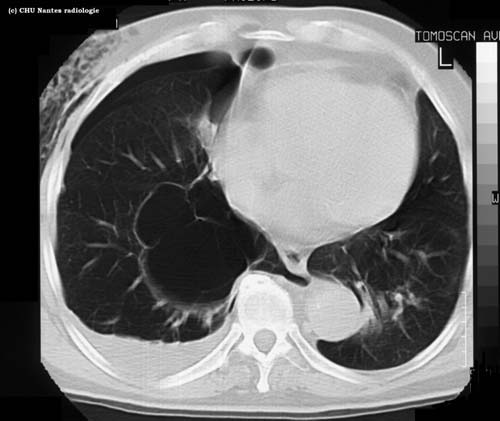

Pneumothorax : coupe

TDM

niveau de la coupe